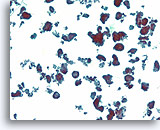

Fibroadenoom, Borst FNA, ThinPrep®.

De ductale cellen zijn geordend in een ‘hertshoornvaren’ of een configuratie van stompe, vertakte gangen. Verspreide naakte myoepitheliale cellen kunnen net in de achtergrond worden onderscheiden.

Fibroadenoom, Borst FNA, ThinPrep®.

De ductale cellen zijn geordend in een ‘hertshoornvaren’ of een configuratie van stompe, vertakte gangen. Verspreide naakte myoepitheliale cellen kunnen net in de achtergrond worden onderscheiden.